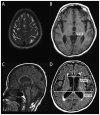

Purpose of review: This article provides neurologists with a pragmatic approach to the diagnosis and treatment of idiopathic normal pressure hydrocephalus (iNPH), including an overview of: (1) key symptoms and examination and radiologic findings; (2) use of appropriate tests to determine the patient's likelihood of shunt responsiveness; (3) appropriate referral to tertiary centers with expertise in complex iNPH; and (4) the contribution of neurologists to the care of patients with iNPH following shunt surgery.

Recent findings: The prevalence of iNPH is higher than previously estimated; however, only a fraction of persons with the disorder receive shunt surgery. iNPH should be considered as a diagnosis for patients with unexplained symmetric gait disturbance, a frontal-subcortical pattern of cognitive impairment, and urinary urge incontinence, whose MRI scans show enlarged ventricles and whose comorbidities are not sufficient to explain their symptoms. Physiologically based tests, such as the tap test (large-volume lumbar puncture) or temporary spinal catheter insertion for external lumbar drainage with gait testing before and after CSF removal, or CSF infusion testing for measurement of CSF outflow resistance, can reliably identify patients who are likely to respond to shunt surgery. Properly selected patients have an 80% to 90% chance of responding to shunt surgery, and all symptoms can improve following shunt surgery. Longitudinal care involves investigating the differential diagnosis of any symptoms that either fail to respond to shunt surgery or that worsen after initial improvement from shunt surgery.